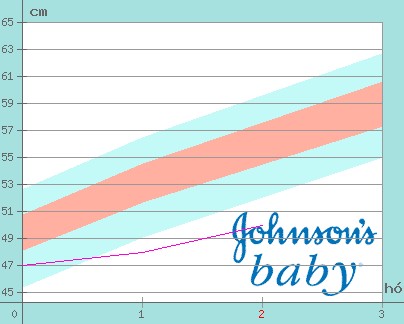

Nálunk Emese:4280gr,Adél:3960gr.Érdekes,hogy születésük óta tartják a 300 gr körüli különbséget.